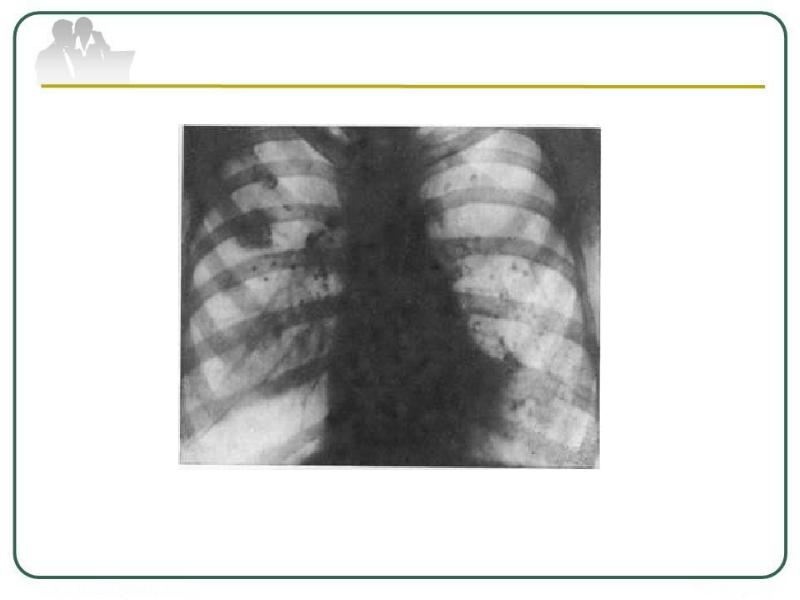

Очаговый и инфильтративный туберкулез презентация - 94 фото